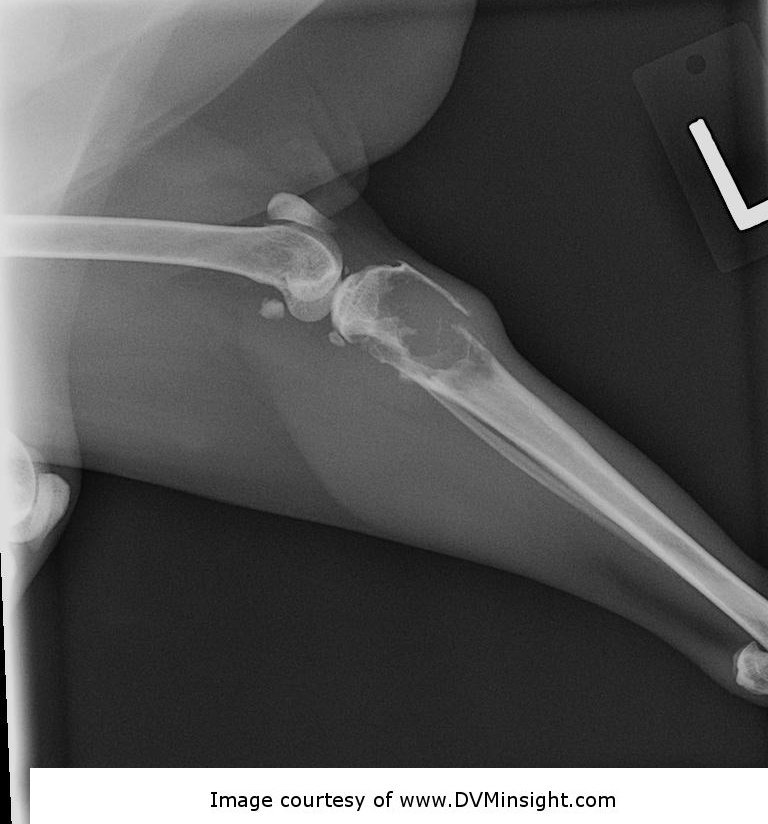

A 12-year old female spayed Himalayan cat presents to you for acute onset of left hind limb lameness after leaping off of the counter to the floor this morning. The cat is non-weight bearing and very painful around the left stifle. You take a radiograph (shown below). Which of the following conclusions can you make about the cat’s injury?

a. The cat has a bone tumor that will likely metastasize within 6 months if she is not given chemotherapy

b. This fracture could be reduced and surgically plated or would heal after 8 weeks with strict confinement with external coaptation

c. Strict rest appears to be all that is needed because the bony structures appear normal

d. A pathologic fracture occurred when the cat jumped off of the counter

A

d. A pathologic fracture occurred when the cat jumped off of the

There is marked osteolysis of the proximal tibia with a pathologic fracture. This fracture will not heal with either rest or with rigid fixation due to the presence of underlying disease that resulted in the osteolysis. The most likely cause is a tumor of the bone. In cats, unlike dogs, many bone tumors do not have a high metastatic rate and do not necessarily require adjunct chemotherapy although histopathology would be needed to confirm the tumor type and grade.